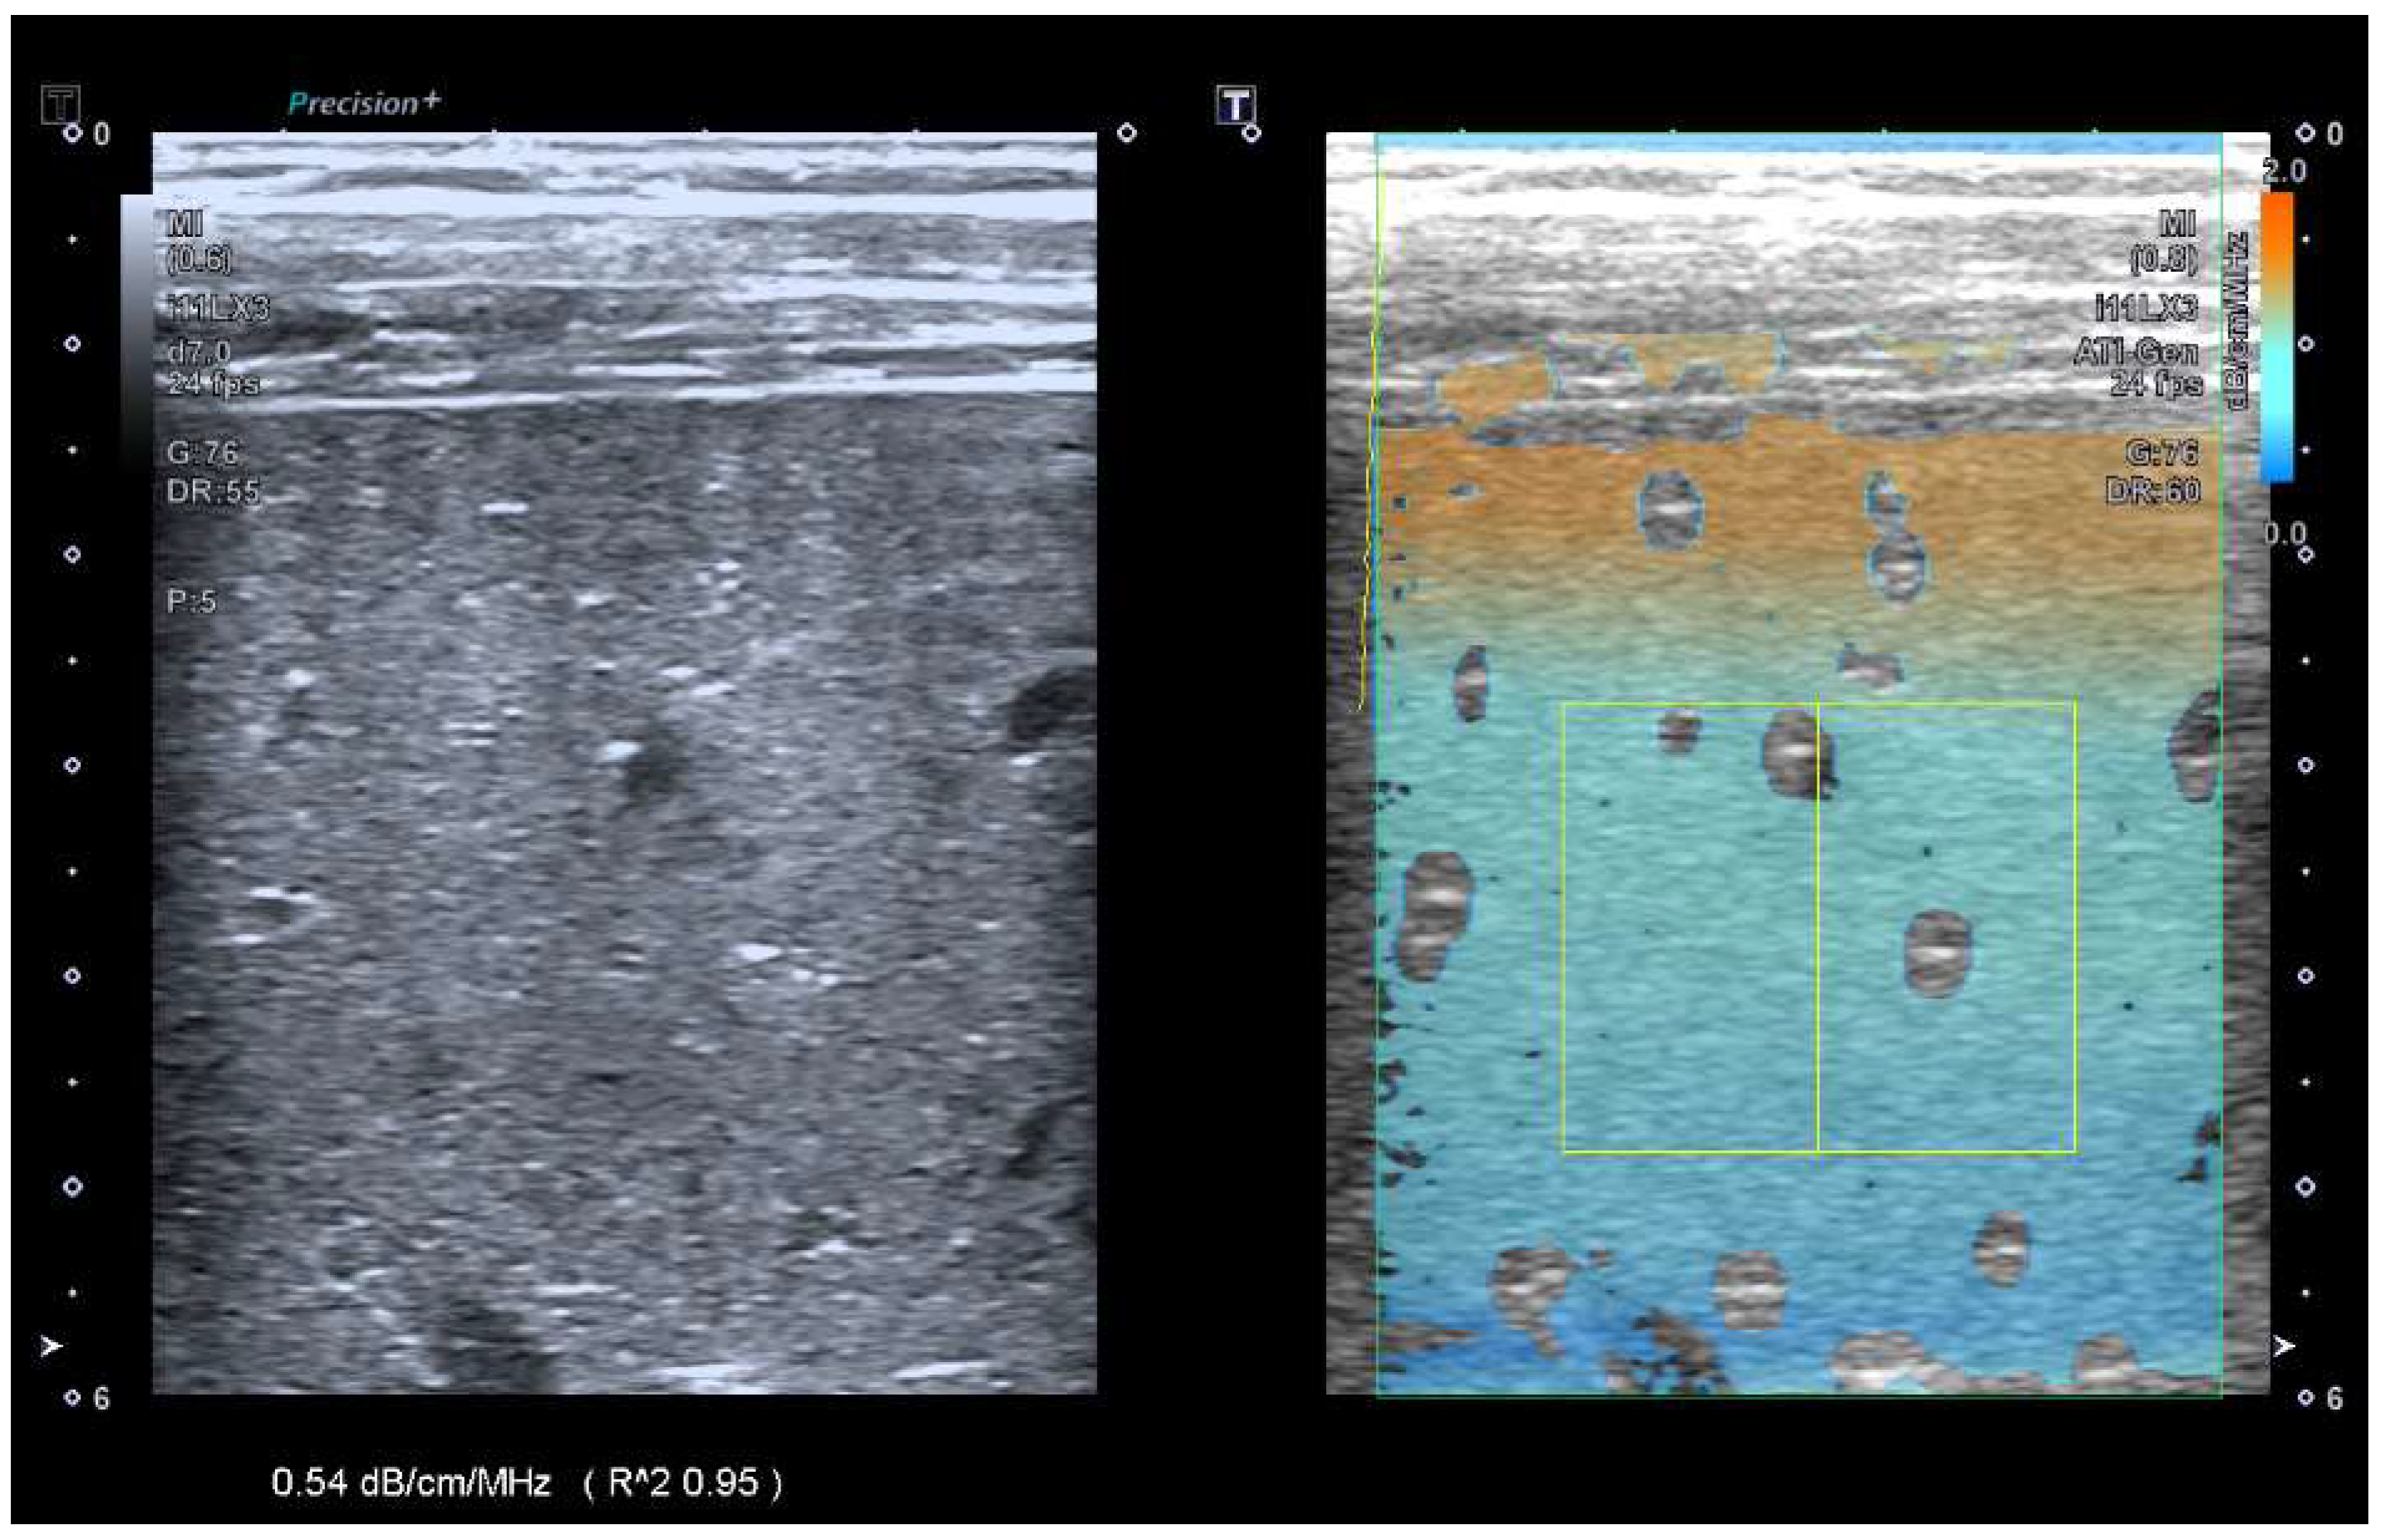

Comparison of Ultrasound Attenuation Imaging Using a Linear versus a Conventional Convex Probe: A Volunteer Study

- Hänni, O.; Ruby, L.; Paverd, C.; Frauenfelder, T.; Rominger, M.B.; Martin, A. Confounders of Ultrasound Attenuation Imaging in a Linear Probe Using the Canon Aplio i800 System: A Phantom Study. Diagnostics 2024, 14, 271. [Google Scholar] [CrossRef] [PubMed]